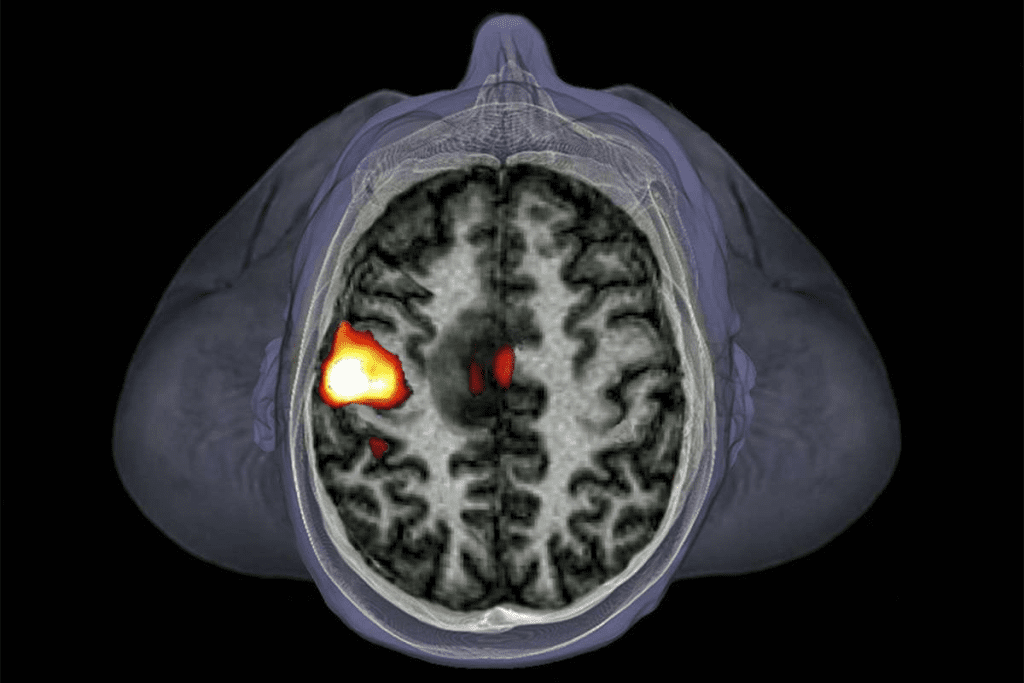

Diagnosing childhood cancer is now more precise and quick thanks to new tech. MRI and CT scans give clear images of tumors. This helps doctors spot cancer better.

Genetic testing is also key in finding out what kind of cancer a child has. It lets doctors create treatment plans that fit each child’s needs.